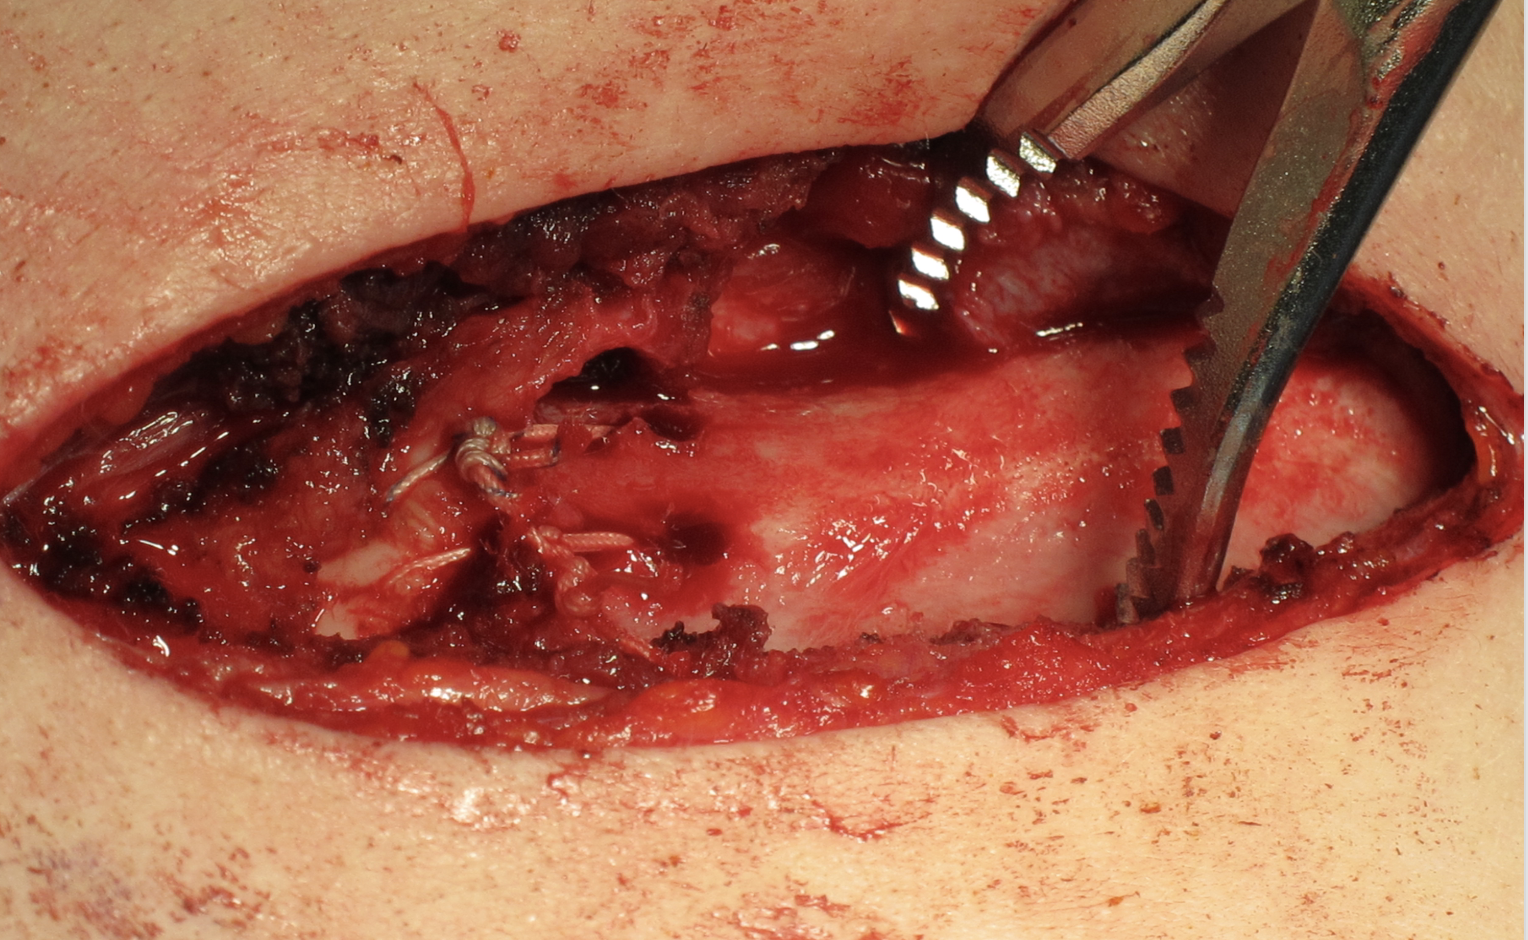

Open reduction of acute posterior sternoclavicular joint dislocation

Drill holes in manubrium and medial clavicle

Figure of 8 suture fixation